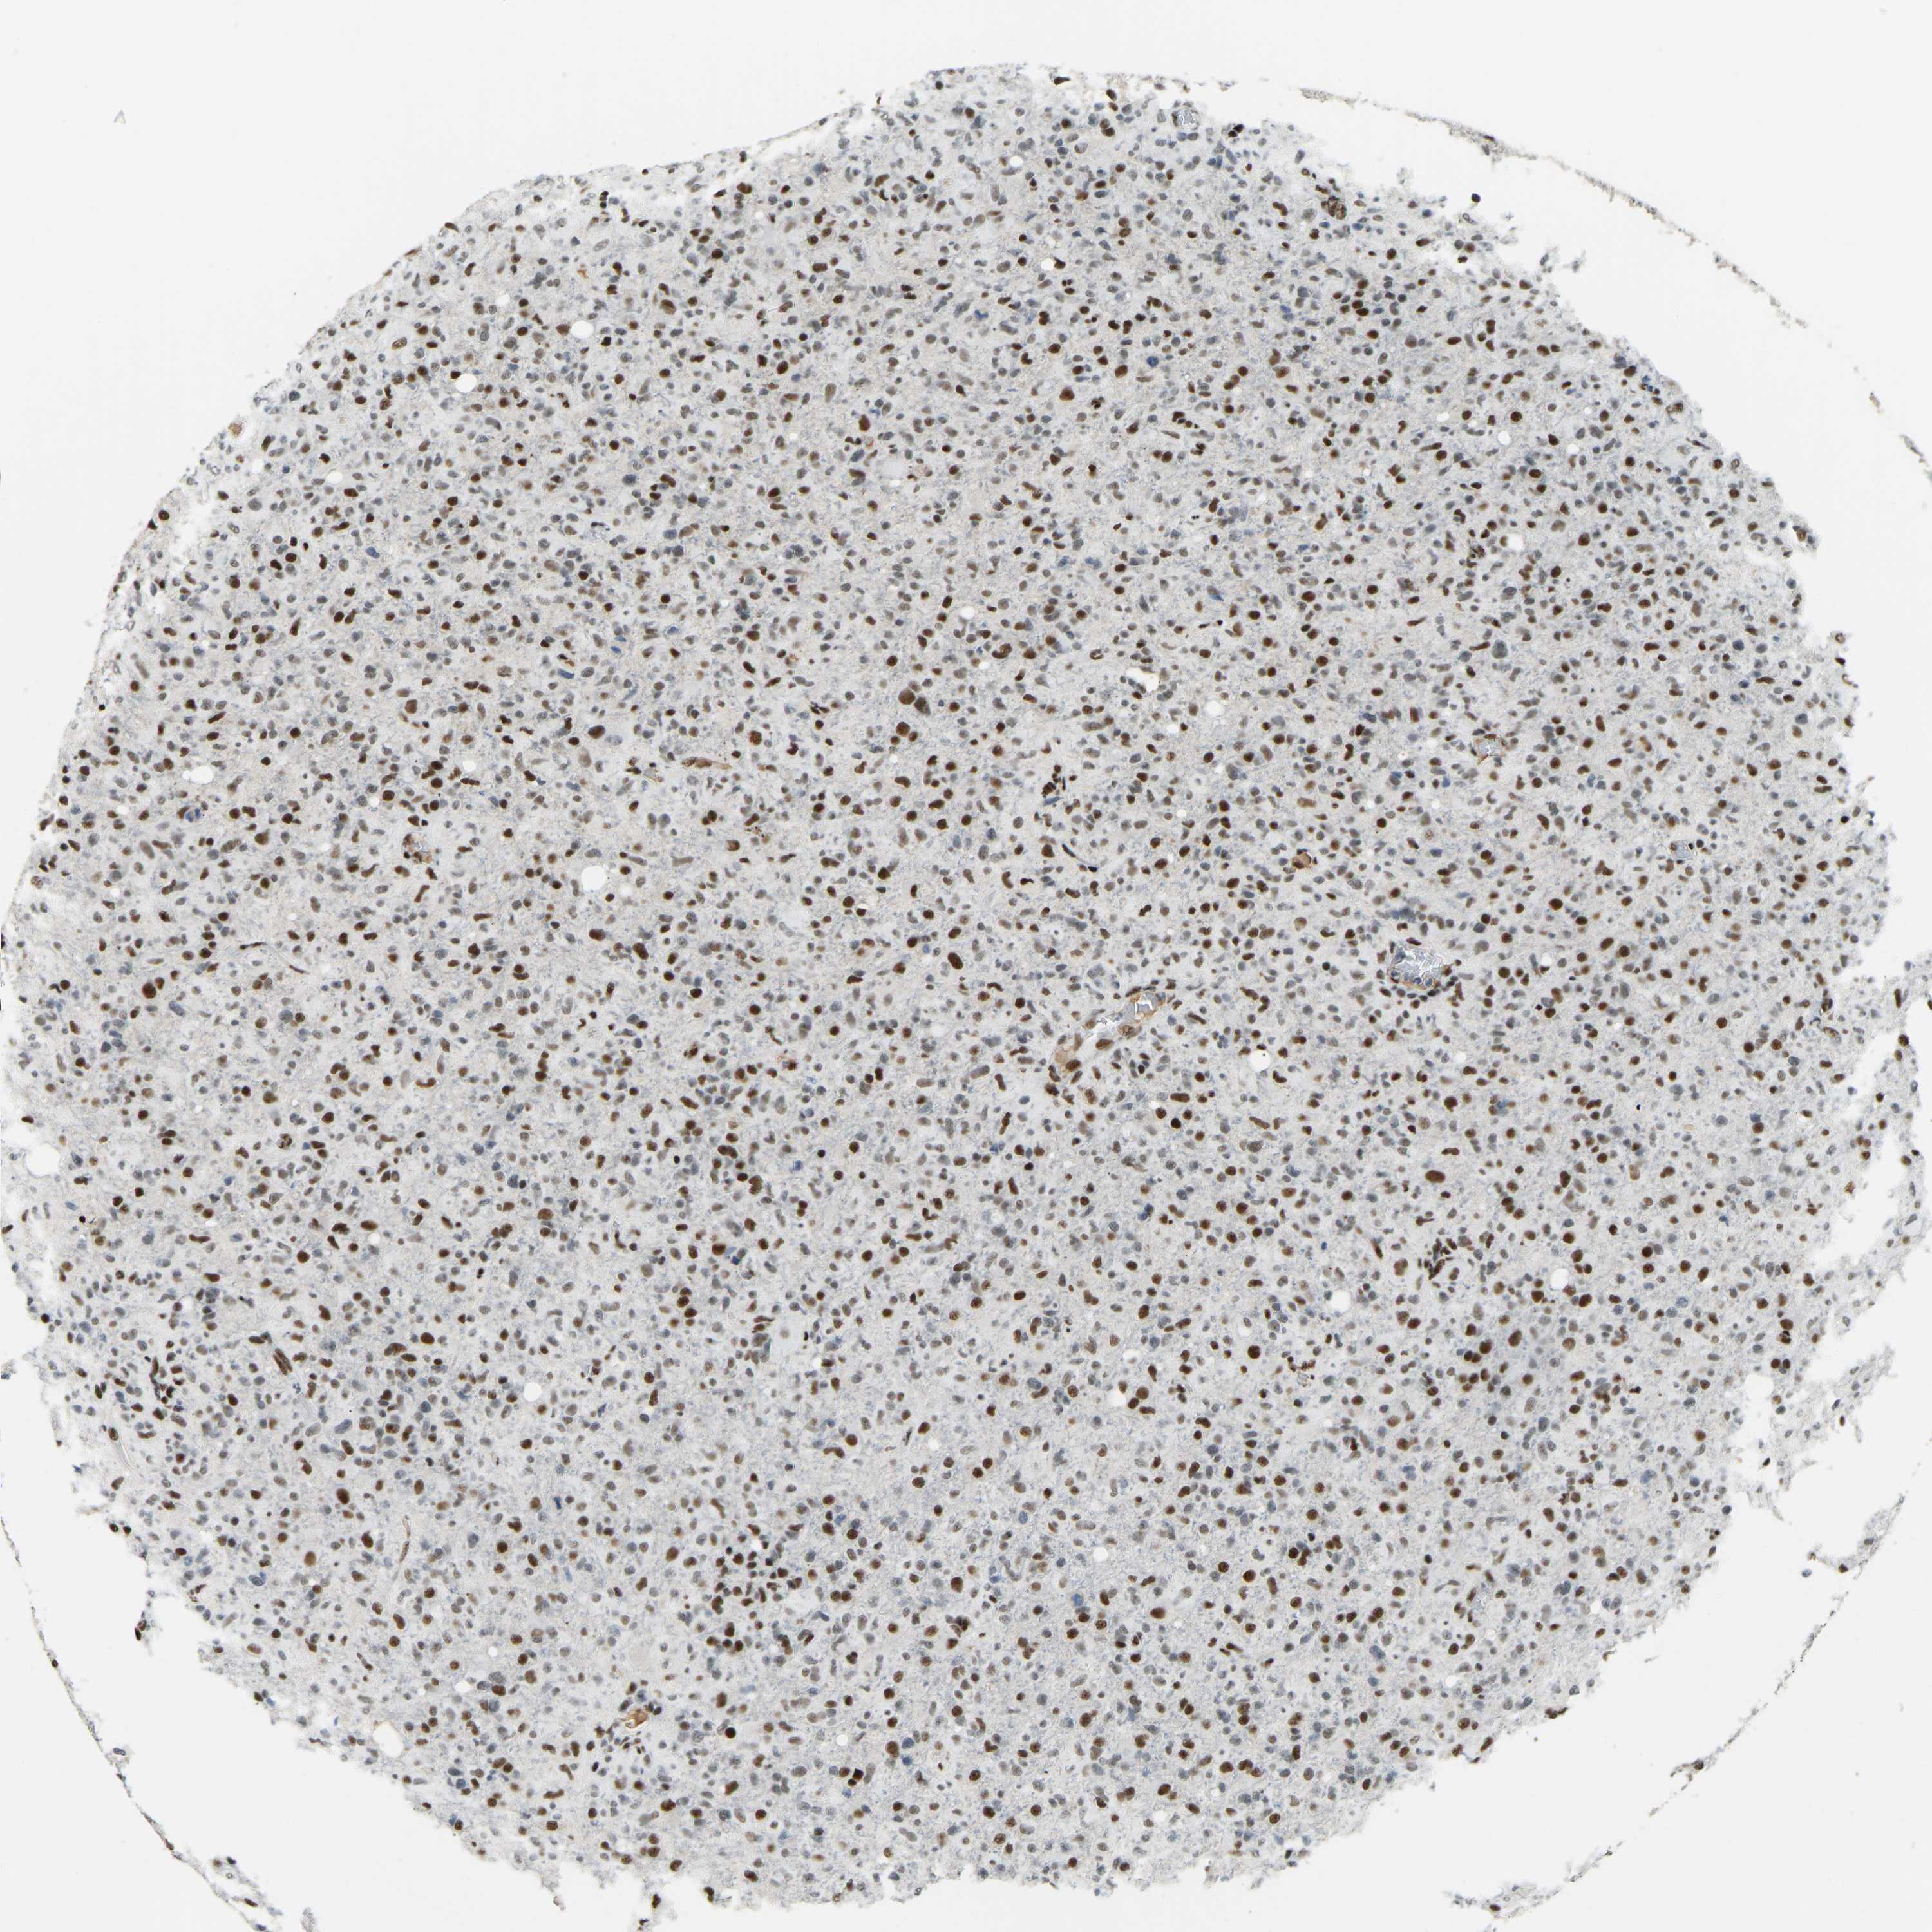

GLIOMA - Protein expressioni

A mouse-over function shows sample information and annotation data. Click on an image to view it in a full screen mode. Samples can be filtered based on level of antibody staining by selecting one or several of the following categories: high, medium, low and not detected. The assay and annotation is described here.

Note that samples used for immunohistochemistry by the Human Protein Atlas do not correspond to samples in the TCGA dataset.

Antibody stainingi

Antibody staining in the annotated cell types in the current human tissue is reported as not detected, low, medium, or high, based on conventional immunohistochemistry profiling in selected tissues. This score is based on the combination of the staining intensity and fraction of stained cells.

Each image is clickable and will lead to virtual microscopy that enables deeper exploration of all samples and also displays staining intensity scores, fraction scores and subcellular localization as well as patient and tissue information for each sample.

Antibody HPA017998

Antibody HPA018864

Staining

High

Medium

Low

Not detected

Intensity

Strong

Moderate

Weak

Negative

Quantity

>75%

75%-25%

<25%

None

Location

Nuclear

Cytoplasmic/membranous

Cytoplasmic/membranous,nuclear

Glioma, malignant, High grade

Glioma, malignant, Low grade